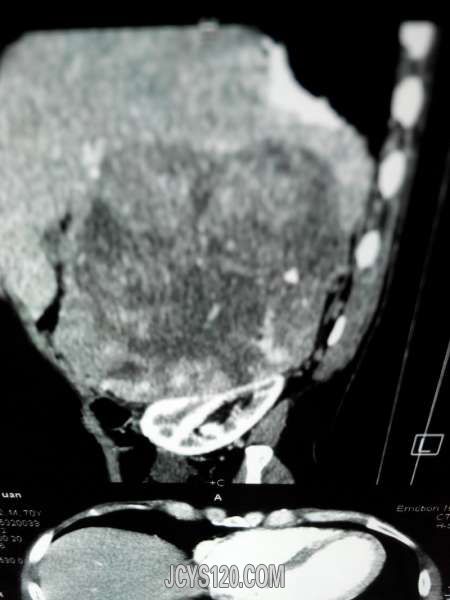

患者女性,70岁,体检发现,大家诊断什么病,怎么治疗。谢谢!